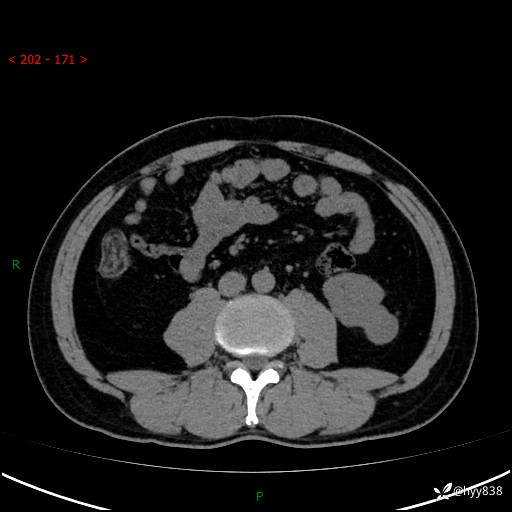

中年男性,左侧腰背部间断性胀痛不适。第一眼“乳头或囊肿”,有无意外---(有结果)

【患者信息】:41岁/男

【主诉】:左侧腰背部间断性胀痛不适1周

【现病史及既往史】:患者1周前无明显诱因出现左侧腰部疼痛,呈间断性胀痛,休息后可缓解,无放射痛,偶可见肉眼血尿,无血块,无尿频尿急尿痛,无夜尿增多,无畏寒发热、咳嗽咳痰等症状。于我院查双肾CT示:左肾占位性病变,左肾下极囊性病变,左肾轻度积水,胆囊多发结石。今为求进一步诊治来我院,门诊以“左肾占位性病变”收治入院。 起病以来,患者精神佳,饮食、睡眠良好,大便正常,小便如上诉,体力体重无明显变化。

【检查】:肾脏CT平扫+增强